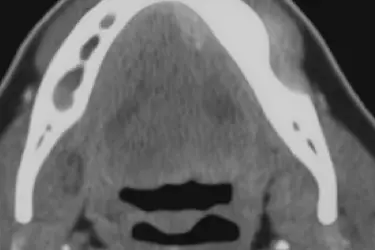

TAC de senos maxilares

Evaluamos los senos paranasales mediante un TAC nasosinusal, especialmente importante para planificar implantes en la zona posterior del maxilar superior.

El TAC de senos maxilares permite valorar el grosor y la anatomía interna del seno, identificando posibles irregularidades o zonas con escaso volumen óseo que podrían dificultar la colocación de implantes.

También ayuda a detectar la presencia de quistes, infecciones o engrosamientos de la membrana sinusal.